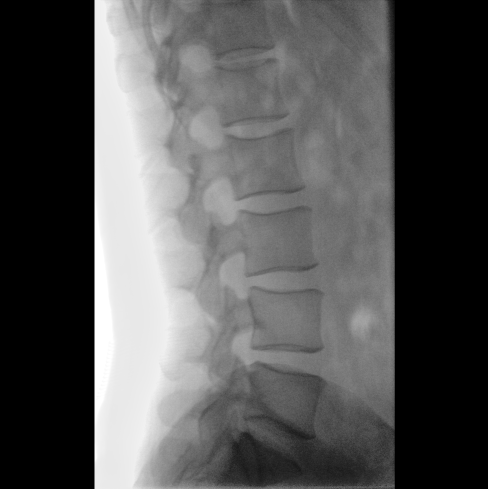

臨床應(yīng)用廣泛,適用于關(guān)節(jié)手術(shù)、創(chuàng)傷手術(shù)、脊柱手術(shù)、疼痛治療等。

●屏幕內(nèi)置DICOM醫(yī)學(xué)曲線,幫助辨認(rèn)細(xì)微組織的密度變化。

●27英寸大尺寸顯示器,更大視野,方便觀察微小結(jié)構(gòu)。

●一屏雙顯,可同時觀察正側(cè)位圖像,便于對比觀察。